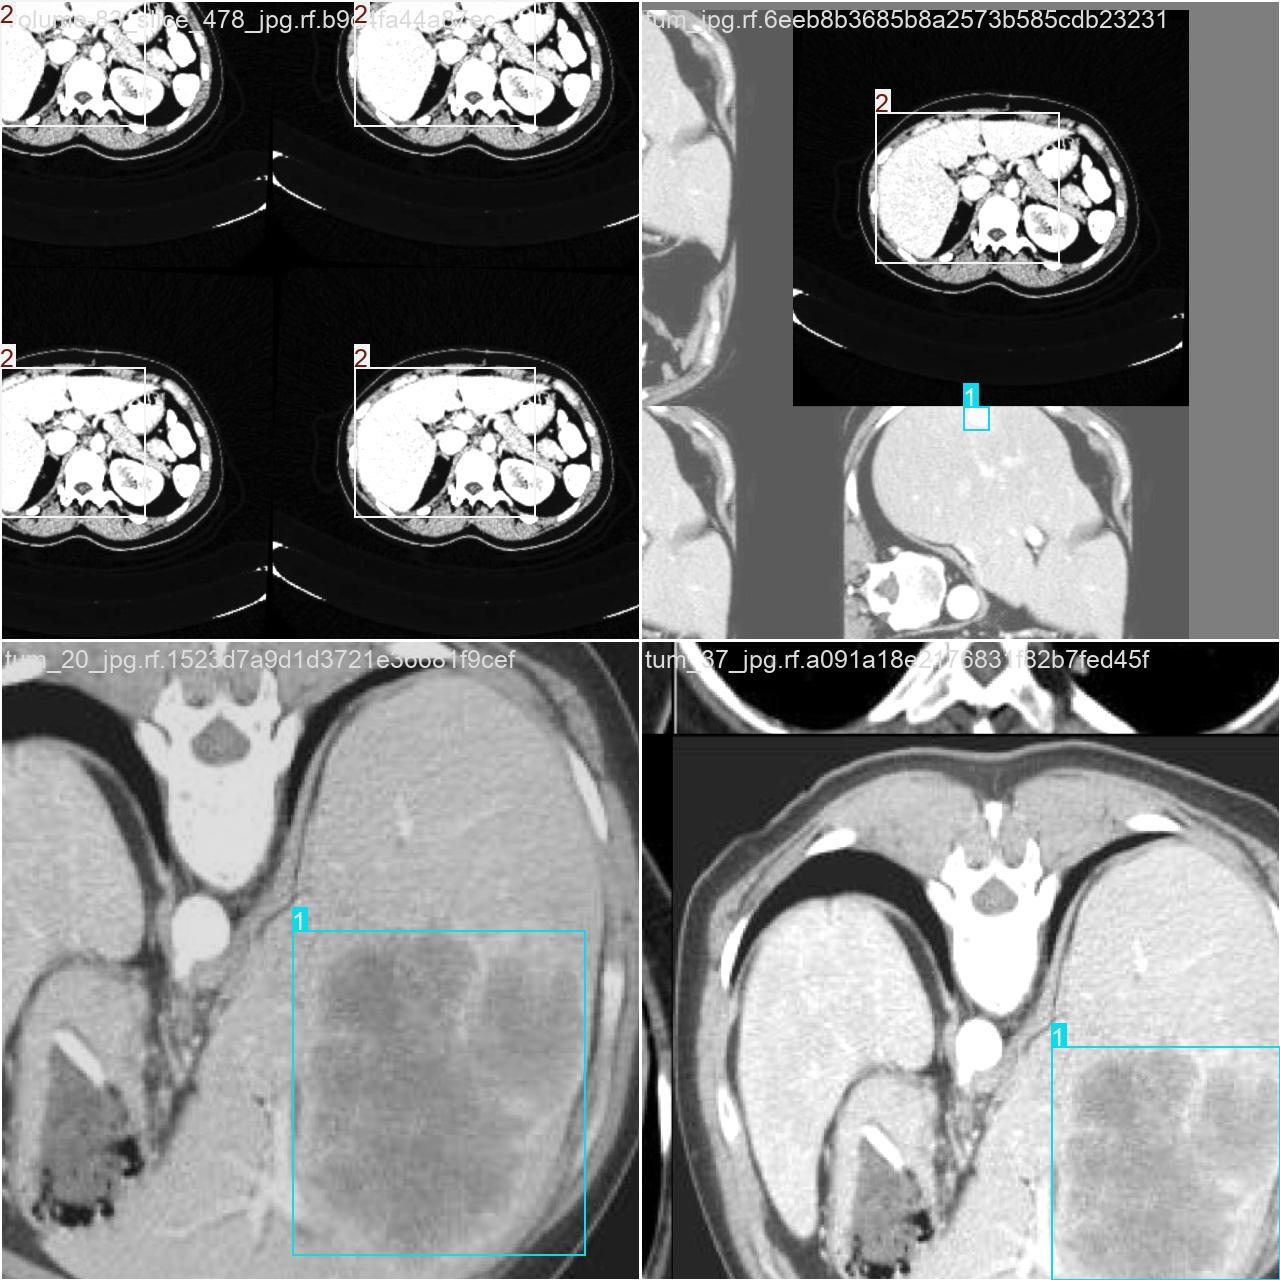

2.数据集准备与训练

本研究使用了包含各肝脏病症相关图像的数据集,并通过Labelimg标注工具对每张图像中的目标边框(Bounding Box)及其类别进行标注。然后主要基于YOLOv8n这种模型进行模型的训练,训练完成后对模型在验证集上的表现进行全面的性能评估及对比分析。模型训练和评估流程基本一致,包括:数据集准备、模型训练、模型评估。本次标注的目标类别为肝脏病症,数据集中共计包含12800张图像,其中训练集占10171张,验证集占2629张。部分图像如下图所示:

部分标注如下图所示: